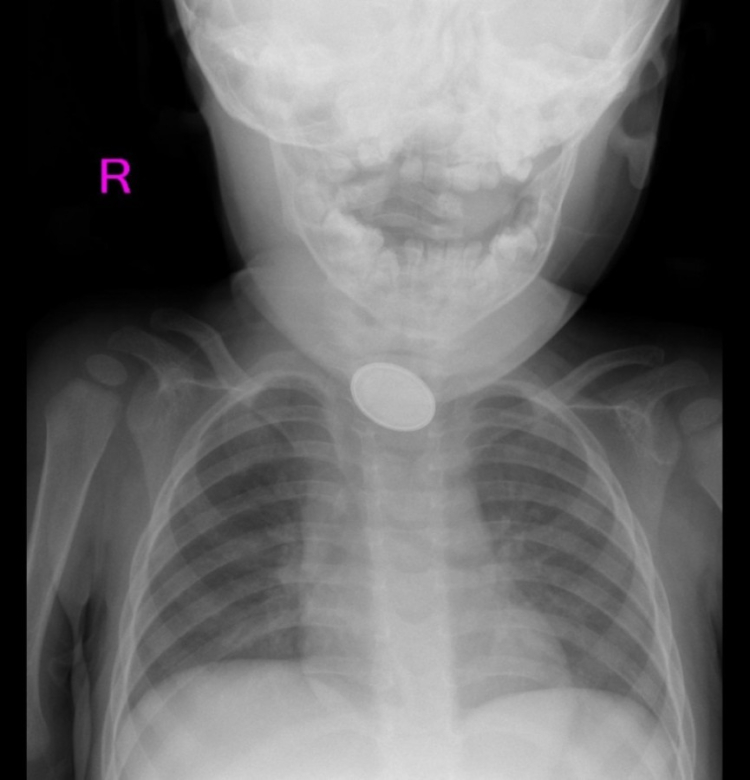

A.Y.Ç.'ye yapılan röntgende, yemek borusunda düğme pil ve lego parçası oyuncağa rastlandı. Kız bebek A.Y.Ç., Kayseri Şehir Hastanesi Çocuk Cerrahisi ve Ürolojisi Anabilim Dalı Başkanı Doç. Dr. Mustafa Erman Dörterler ve ekibi tarafından ameliyata alındı.